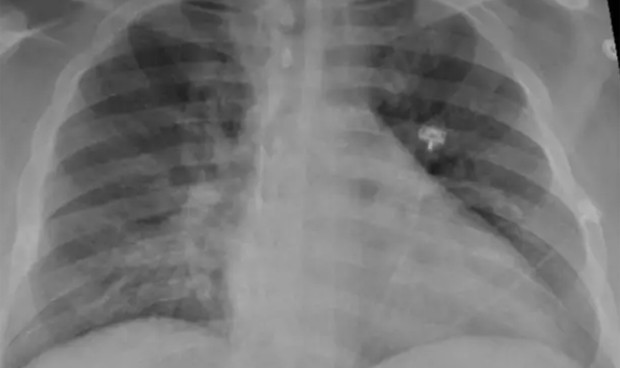

La radiografía de tórax de un paciente positivo de Covid-19 que muestra una neumonía en la parte inferior de los pulmones.

En lugar de infectar rápidamente grandes regiones del pulmón, tal y como hace la neumonía convencional, el SARS-CoV-2 se instala en múltiples pequeñas áreas del pulmón. A partir de ahí, el virus secuestra las propias células inmunes de los pulmones y las usa para propagarse por el pulmón durante un largo periodo de tiempo. Los investigadores usan el ejemplo grafico de un incendio forestal. Es decir, el Covid-19 sería como un foco que se va provocando lentamente otros focos. Esos otros focos serían los otros órganos que se ven afectados por el virus, como los riñones, el cerebro, o el corazón.